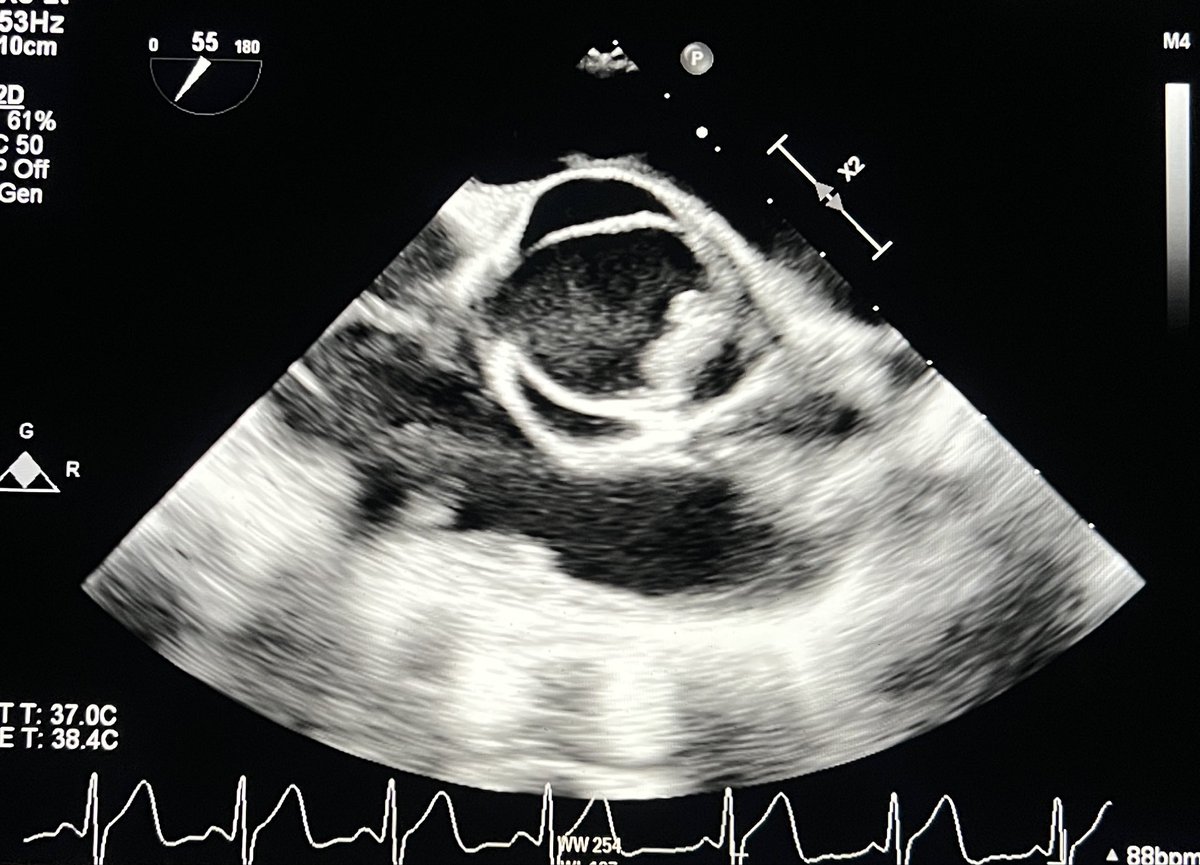

#echofirst ✅ Annuloplasty can be done with a band (incomplete circle on echo) or a ring (complete circle) ✅ 3D example of MV annuoplasty band ⬇️ with only residual mild MR & no MS ✅ Marked restriction of PML from annuloplasty @argulian @iamritu @purviparwani @PWesslyMD